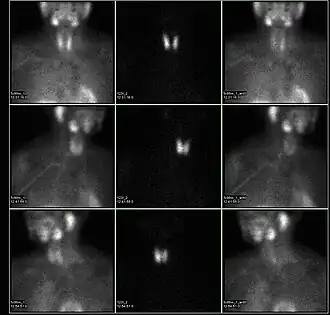

Nuclear medicine myocardial perfusion scan with thallium-201 for the rest images (bottom rows) and Tc-Sestamibi for the stress images (top rows). The nuclear medicine myocardial perfusion scan plays a pivotal role in the non-invasive evaluation of coronary artery disease. The study not only identifies patients with coronary artery disease; it also provides overall prognostic information or overall risk of adverse cardiac events for the patient. -

A nuclear medicine parathyroid scan demonstrates a parathyroid adenoma adjacent to the left inferior pole of the thyroid gland. The above study was performed with Technetium-Sestamibi (1st column) and iodine-123 (2nd column) simultaneous imaging and the subtraction technique (3rd column). -